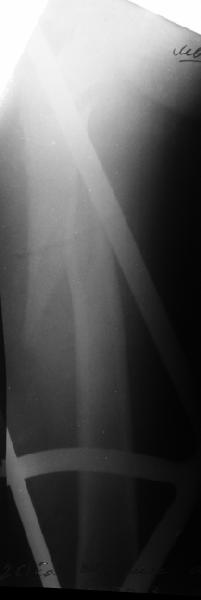

В диагноз пишем... Потом же как-то анализировать надо. Что-то никто не откликнулся на этот вопрос из англоязычных коллег. Все-таки - как такой перелом надо классифицировать? А если шейка бедра + диафиз? Завтра покажу такой случай.

Мы обычно проводим спицу ближе к заднему кортексу - иногда бывает, гвоздь смещается кзади, за фрагменты, особено при многооскольчатых переломах...

Это тоже не делаем. Разве что иногда приходится шилом подтолкнуть промежуточный фрагмент, если он перекрывает вход в дистальный отломок. Но костедержатель засовывать - зачем??? Ведь при введении гвоздя репозиция происходит "автомагически"?